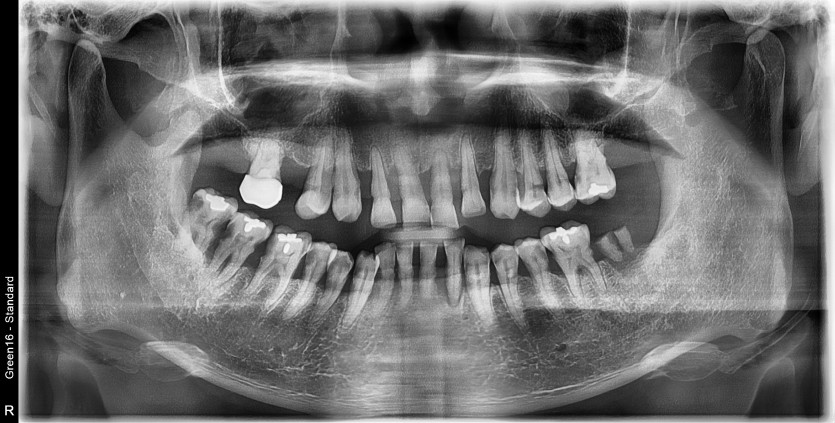

만 53세 전체 임플란트 증례

전체 임플란트 증례입니다.

18개의 임플란트로 완성하였습니다.